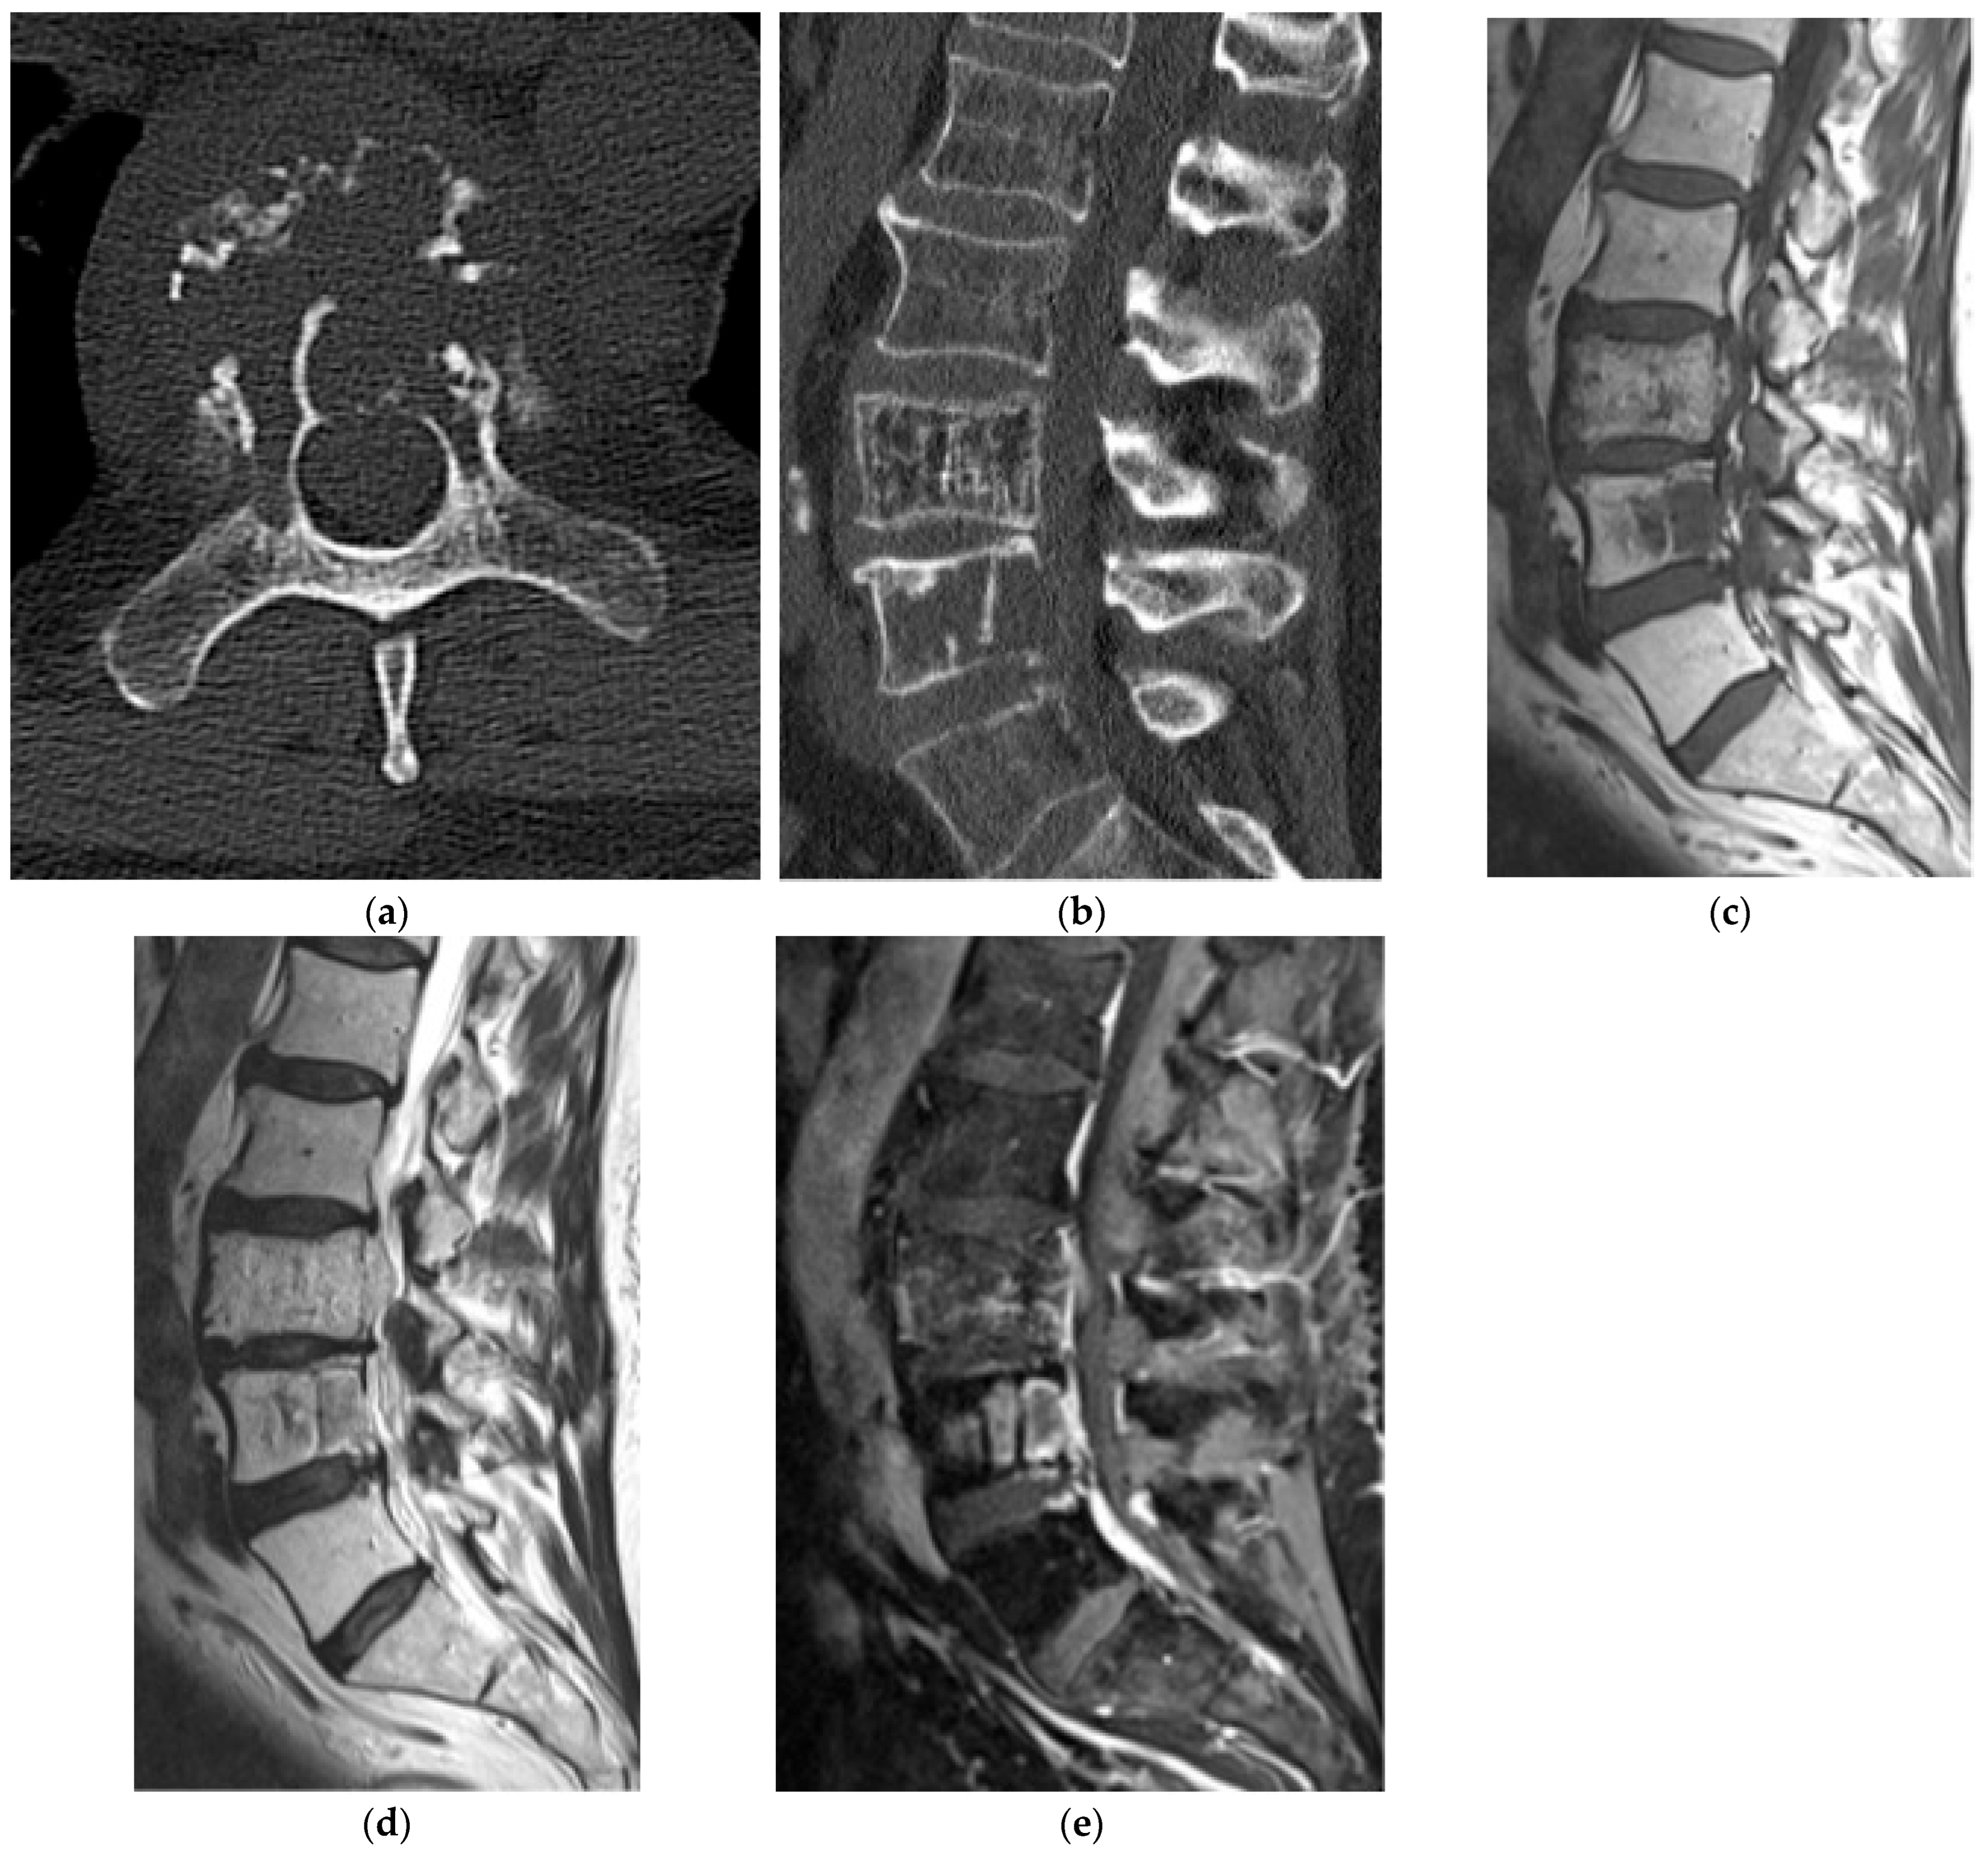

2.2.3. Chondrosarcoma

2.3. Notochordal

2.3.1. Benign Notochordal Cell Tumors (BNCT)

2.3.2. Chordoma